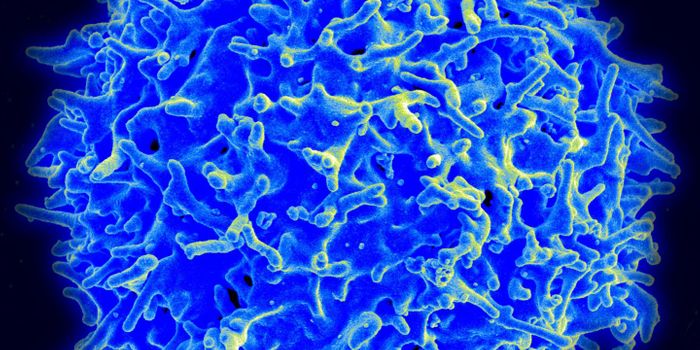

T-Cells

T-Cells: A type of white blood cell that plays an important role in the immune system. They are produced by the thymus gland and help the body fight off viruses, bacteria, and parasites.